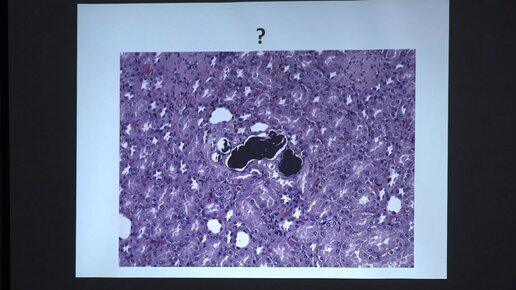

Манских В. Н. - Патология экспериментальных животных - Нарушение кровообращения